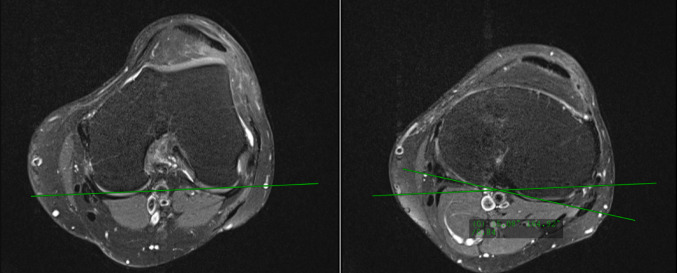

Methods: One-hundred-forty-four knees who underwent patellar stabilizing surgery between January 2010 and December 2020 were retrospectively analysed. Caton-Deschamps index (CDI), tibial-tubercle-trochlear-groove distance (TTTG), tibial tubercle (TT) torsion, tibial tubercle-to-posterior cruciate ligament distance (TT-PCL), and pre- and postoperative FT rotation were assessed. Based on the performed patellar stabilizing procedures, knees were stratified into 4 groups: 1: Isolated medial patella-femoral ligament (MPFL) reconstruction (n = 51), 2: MPFL reconstruction and TTO (n = 24), 3: MPFL reconstruction and trochleoplasty (n = 37), 4: MPFL reconstruction, trochleoplasty, and TTO (n = 32).

Abstract Image